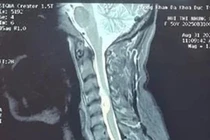

Các bác sĩ Bệnh viện Đa khoa Hòa Bình vừa thực hiện thành công ca mổ lấy khối u màng tủy sống vùng cổ C4/5 – loại u hiếm, vị trí đặc biệt khó.